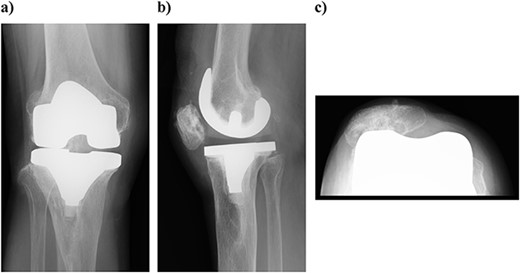

On physical examination, the patient extension and flexion were − 20° and 130°. A defect of the tibial tubercle was observed. The Knee Society (KS) score was 44 points, and the Knee Society function (KS-F) score was 70 points. A plain radiography showed valgus knee osteoarthritis assessed as Kellgren–Lawrence grade 4. In addition, a well-defined translucent image of bone appeared near the central part of the proximal tibia and no tibial tubercle could be observed (Fig. 1). Magnetic resonance imaging (MRI) of the right knee joint showed the patellar tendon appeared from the attachment on the patella with continuity to the tibial bone marrow in T1- and T2-weighted imaging (Fig. 2).

Plain radiography at the patient’s first visit: (a) standing front, (b) lateral side and (c) thigh, standing, front, full length. Valgus knee osteoarthritis and well-defined osteoporosis near the central part of the proximal tibia can be seen, and the rough surface of the tibia has been worn away.